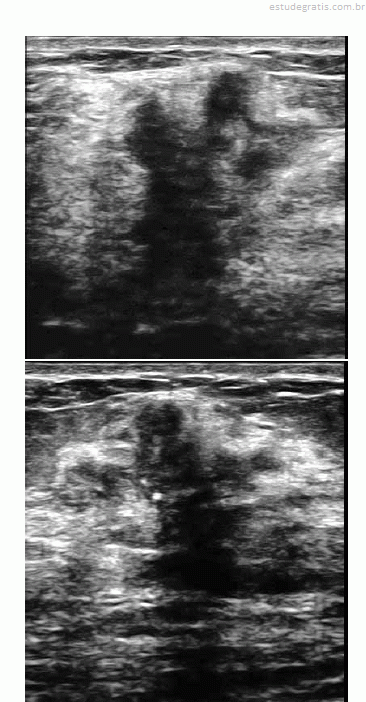

Uma paciente de 32 anos de idade procurou um médico ginecologista por ter palpado nódulo na mama direita. Ao exame das mamas, foi percebido nódulo endurecido, fixo aos planos adjacentes, com cerca de 3 cm de diâmetro. Foi realizada, então, mamografia, que revelou presença de lesão espiculada, com limites imprecisos, retração do parênquima adjacente e microcalcificações pleomórficas agrupadas. O exame ultrassonográfico evidenciou a lesão representada na forma gráfica na figura abaixo.